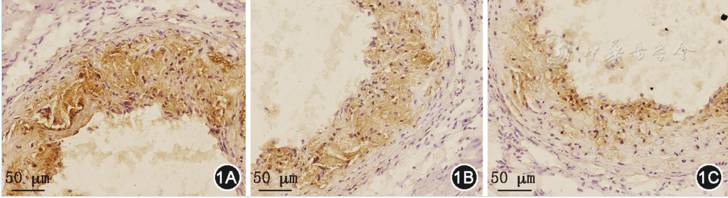

5.主动脉根部内皮素1和VEGF的蛋白表达水平(图1、图2,表5):

图1 免疫组织化学法检测主动脉根部的内皮素1表达(1A:对照组;1B:低剂量补硒组;1C:高剂量补硒组;棕色区域为内皮素1蛋白表达)

高剂量补硒组和低剂量补硒组的内皮素1蛋白表达水平均低于对照组,且高剂量补硒组的内皮素1蛋白表达水平低于低剂量补硒组(P均0.05)。